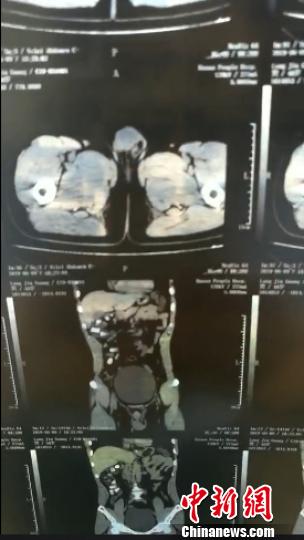

经X光检查,龙某体内有大量可疑固体柱状物品。

经X光检查,龙某体内发现有大量可疑固体柱状物品。据医生介绍,这符合体内毒品破裂的症状。经抢救,并通过近8天的“排毒”,龙某先后10多次从体内排出61颗用透明胶包裹缠绕的“香肠”。经技术鉴定,这些香肠包裹的系毒品海洛因,净重294.54克。